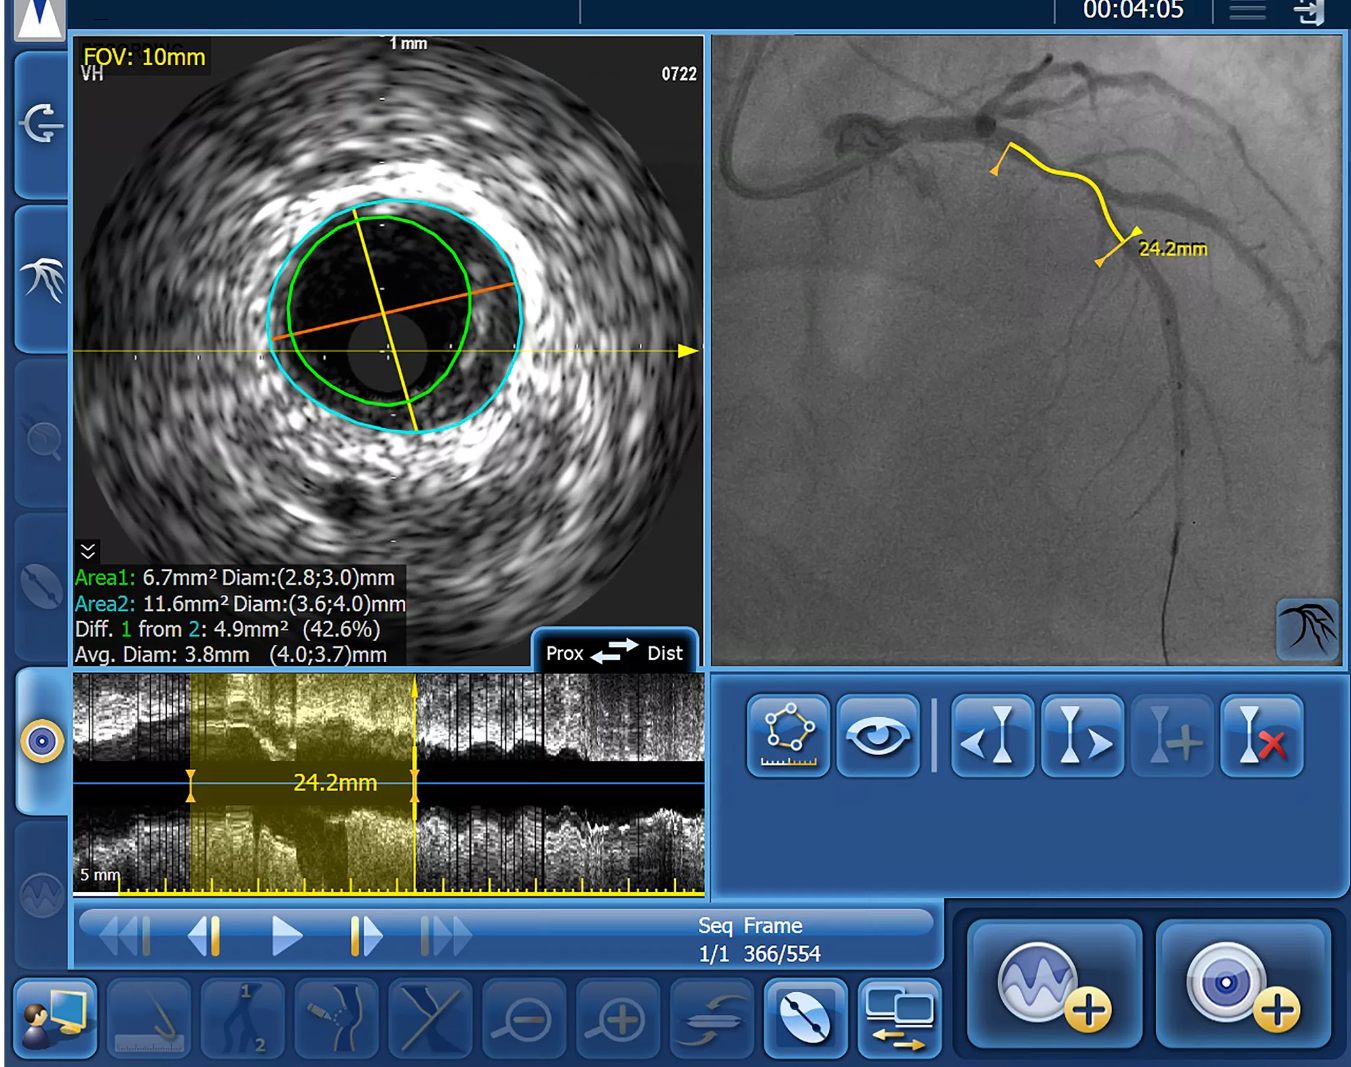

Система для высокоточного управляемого лечения SyncVision оптимизирует процесс оценки пораженных участков, облегчает определение размеров сосудов и обеспечивает точное проведение терапии в сочетании с существующим процессом получения рентгеноскопических изображений.

- Функция локализации с помощью совмещения данных ВСУЗИ системы SyncVision

- Облегчение определения размера/измерения характеристик сосуда

Комплекс включает специальные средства, помогающие врачам повысить эффективность чрескожных коронарных вмешательств (ЧКВ) как на диагностическом, так и на этапах лечения. SyncVision — универсальное средство, позволяющее решать вопросы получения изображений и определения физиологических параметров в катетеризационной лаборатории. SyncVision позволяет планировать стратегию ЧКВ, путем картирования результатов внутрисосудистого исследования и измерения физиологических параметров кровотока на ангиографическом изображении. Кроме того, способствует выполнению целенаправленной оценки поражения, упрощает определение размеров сосуда и повышает точность лечебной процедуры.